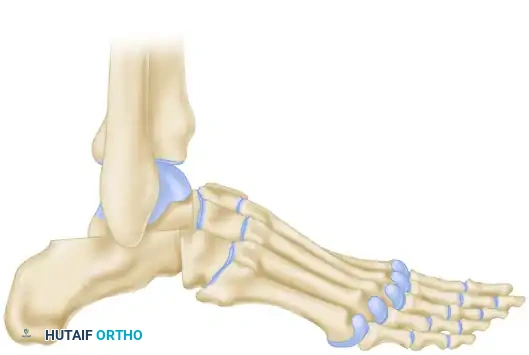

Dunn Arthrodesis

The Dunn arthrodesis is a powerful technique designed specifically to address severe cavus by shortening the foot and shifting the pivot point.

The skin incision is made laterally, and a substantial amount of bone is resected, specifically targeting the complete excision of the navicular.

By removing the navicular, the medial column is drastically shortened.

The foot (excluding the talus) is then displaced posteriorly at the subtalar joint.

In the final reconstructed position, the head of the talus is apposed directly to the cuneiforms. This posterior displacement of the foot relative to the talus restores a plantigrade weight-bearing surface and significantly improves the biomechanical advantage of the posterior calf musculature.